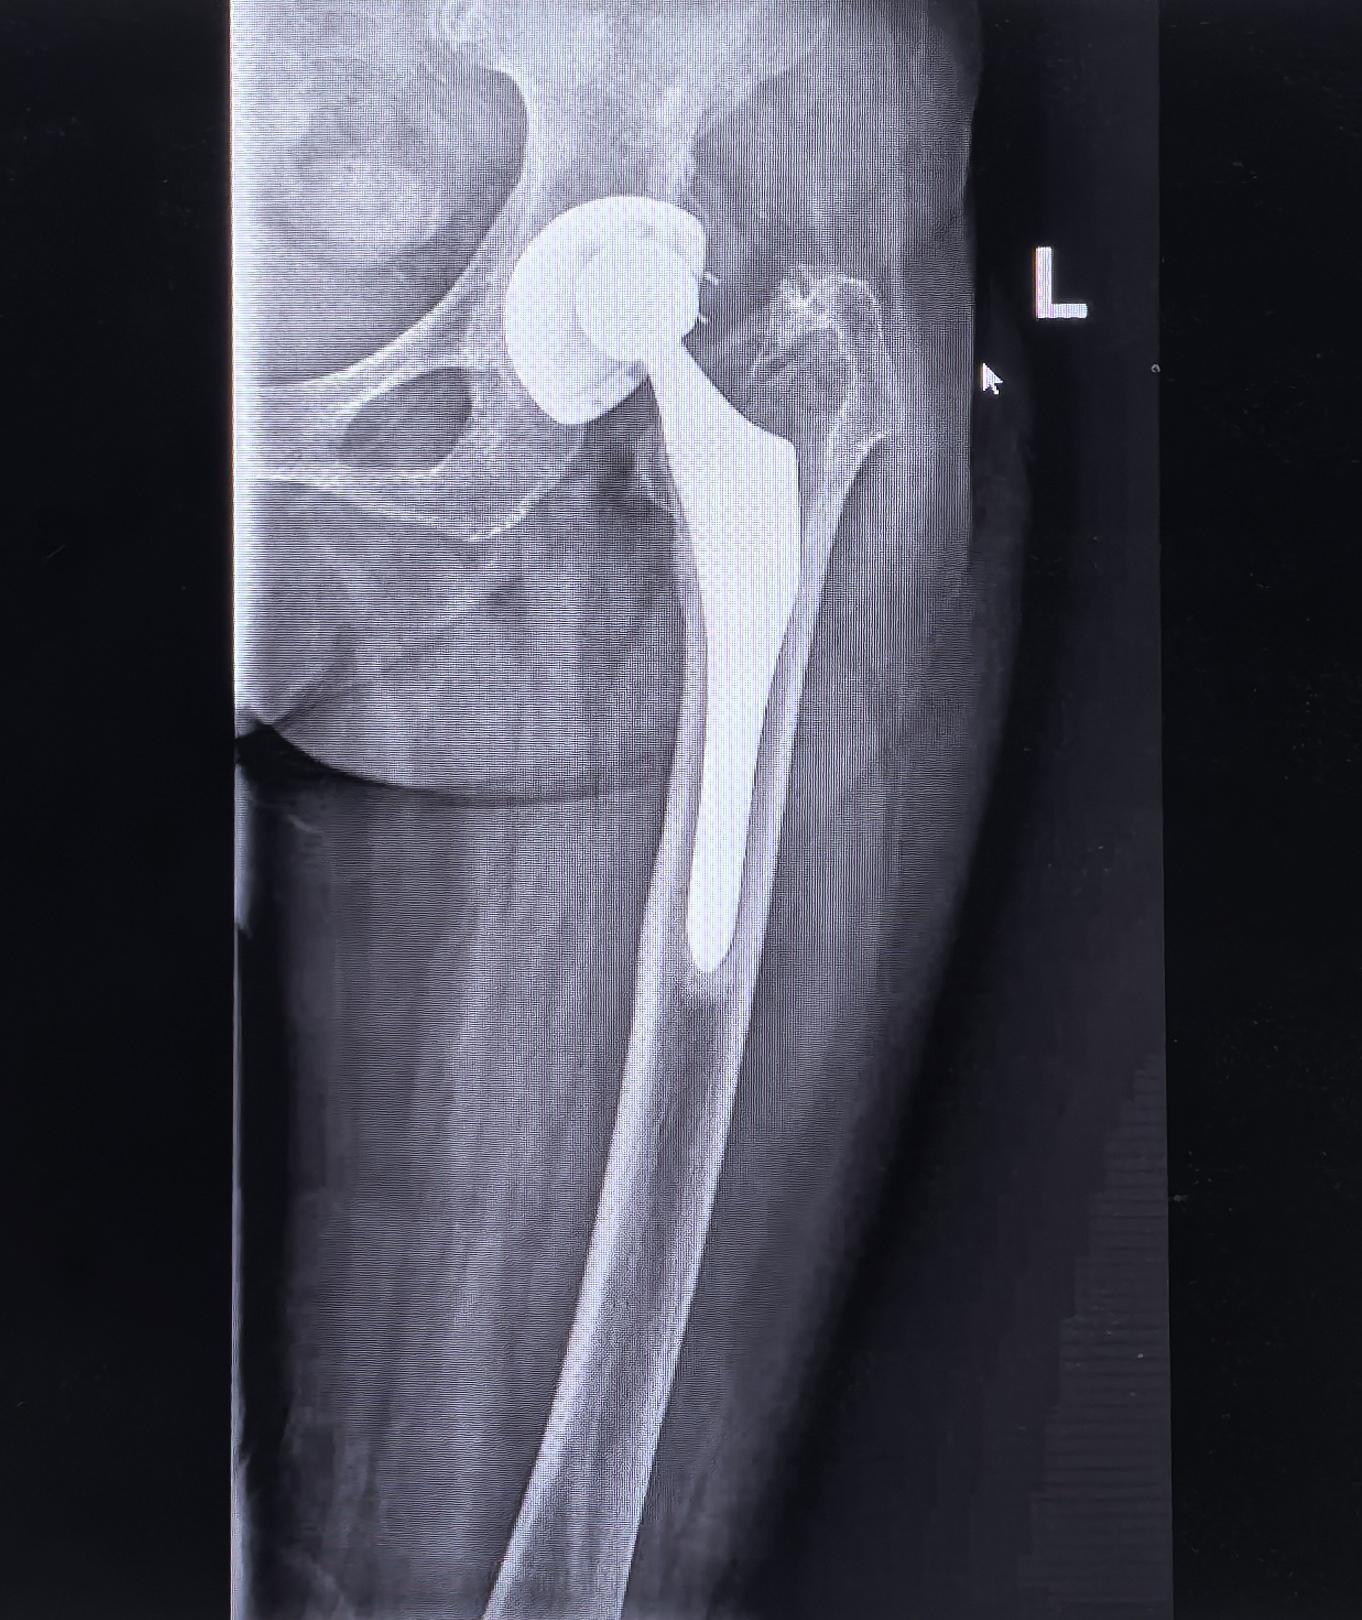

髋关节翻修,髋关节置换。股骨头坏死髋关节置换术后22年假体松动,83岁高龄二次翻修,手术顺利,再次“续命”20年🌹